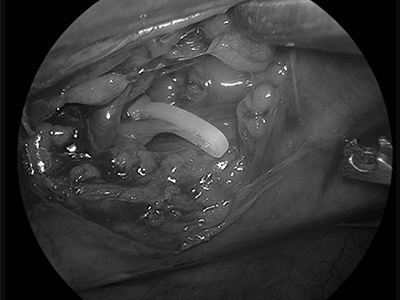

흉강경 Thoracoscopy 흉강

흉강경은 최소 절개를 통해 내시경으로 병변을 진단하고 치료하는 정밀 수술입니다. 통증과 출혈을 최소화하고 회복 기간을 단축합니다.

개흉술(thoracotomy)에 비해 덜 침습적으로 흉강 내부를 진단하거나 수술할 수 있는 방법으로 폐엽절제(lobectomy), 흉막생검, 심낭절제(pericardiectomy), 흉관결찰술(thoracic duct ligation) 등이 가능합니다.

흉강경

흉강경 수술 장면 이미지

흉강경 장비 및 시술 장면 이미지